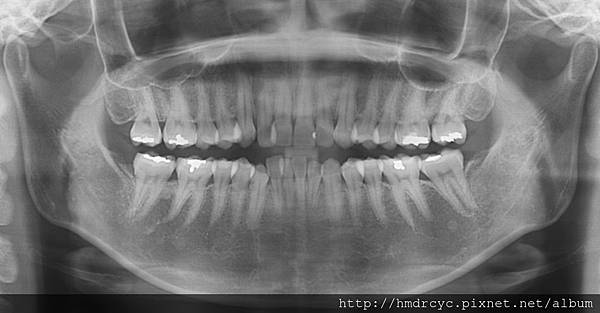

首先必須X光片評估之前填補的深度

是否已經很靠近神經

否則若填補太深 刺激神經

反而不補不痛 補完開始敏感

事前的評估完成無慮後